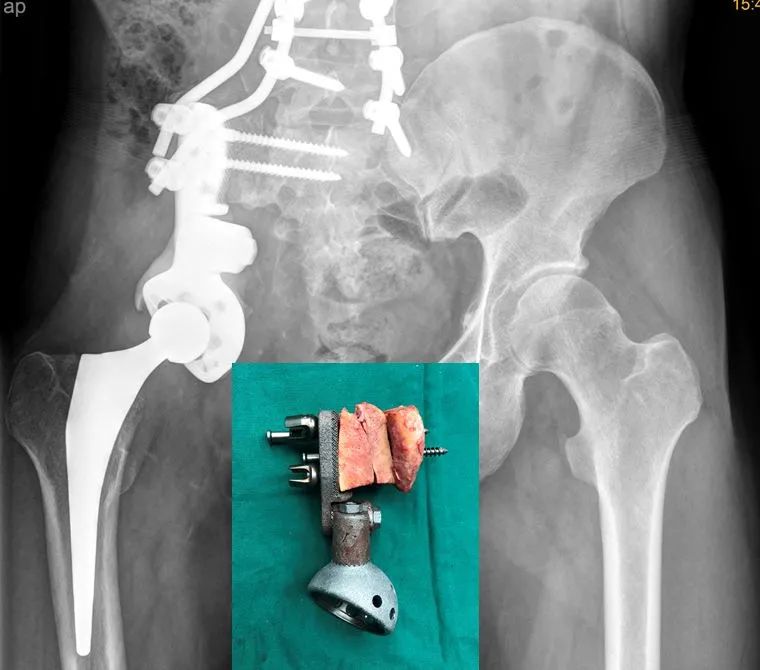

这个肿瘤有多大?有“排球大”!

这颗“排球”叫做“恶性软骨肉瘤”,也就是人们俗称的“骨癌”。

影像检查显示,这颗肿瘤占满了整个右边臀部,完全填塞坐骨大孔及闭孔,使髂血管、坐骨神经及盆腔内脏受压移位。而肿瘤病变在前方还越过耻骨联合累及膀胱、侵犯髋关节,膀胱受压后容积缩小近一半;在后方越过骶髂关节累及骶骨翼,严重挤压坐骨神经。

“在骨科,专业上把骨盆肿瘤分为四个区,一般的骨盆肿瘤患者的肿瘤只长在一个区或者两三个区,但涂先生的肿瘤却极罕见的累及骨盆全部四个区,而且重要神经、血管和器官都受压移位,已具备高位半骨盆截肢的指征。以前这些区域手术风险太大,是公认的手术‘禁区’,没有人敢做。”张世权分析道。

骨盆肿瘤切除重建手术是骨科领域最难的手术之一,过去,骨盆恶性肿瘤患者要想保命,就得截肢。如果要保肢,对于医生来说,这个手术又是一个巨大的挑战。“涉及到骨盆、骶骨、腰椎和髋关节的广泛切除和复杂重建流程,难度极高,风险极大,用到的器械多达上百种。过去在华南地区此类手术尚属空白。”张世权表示。

为了给病人保肢,团队引进了深圳市“医疗卫生三名工程”团队北京大学人民医院骨肿瘤科郭卫教授的最新发明成果——世界首创3D打印组配式人工半骨盆假体。

应用先进的3D打印技术,将粉末状钛合金材料构造成仿骨小梁结构的多孔状假体界面,帮助病人量身订制骨盆假体进行患侧半骨盆置换,从而达到符合生物力学要求的结构与功能重建。

张世权主刀带领团队医生,连续奋战9个小时,顺利完成了这台超高难度手术。